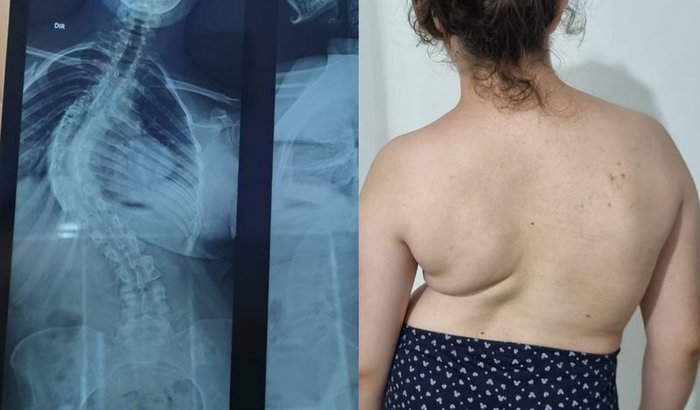

Oie pessoal, meu nome é Vanessa tenho 23 anos sou de Blumenau SC e vou contar um pouco da minha história. A mais ou menos 3 anos atrás fui diagnosticada com Escoliose indiopática do adolescente pelo ortopedista e traumatologista Doutor Fabiano Caumo, onde fui examinada e recebi o diagnóstico e também a resposta que a cura seria apenas cirurgia, então com muita coragem corremos atrás para fazer os exames certinho e o encaminhamento para cirurgia pelo SUS, mas com a demora do SUS decidimos fazer a vakinha, pois sinto muitas dores e não é nenhum pouco fácil conviver com esse problema e por conta disso também estou desempregada é muito mais difícil empresas contratarem pessoas com esse tipo de problema, fizemos o orçamento com meu ortopedista para o tratamento cirúrgico e o valor é de R$146.515,71. Eu sei, o valor parece assustador mas eu creio que com a sua ajuda e com muita fé em Deus conseguirei fazer a minha cirurgia e passar ter uma qualidade de vida muito melhor. Que Deus abençoe a todos em dobro 🙏🏻🙏🏻 Ass: Nessa ❤️‍🩹